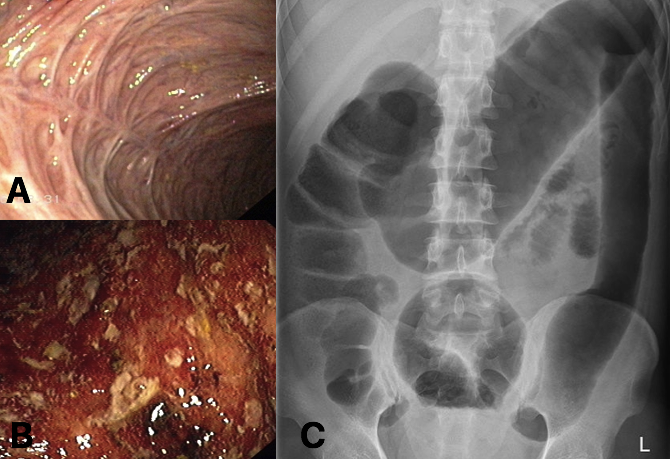

What is shown in image A and B?

Erythema nodosum.

What is shown in image A?

(A) bowel fibrosis, secondary to chronic UC

What is shown in image B?

(B) active inflammation in patient with UC.

What is shown in image C?

(C) AXR changes in active UC, showing toxic megacolon with lead-pipe colon (seen in descending colon).